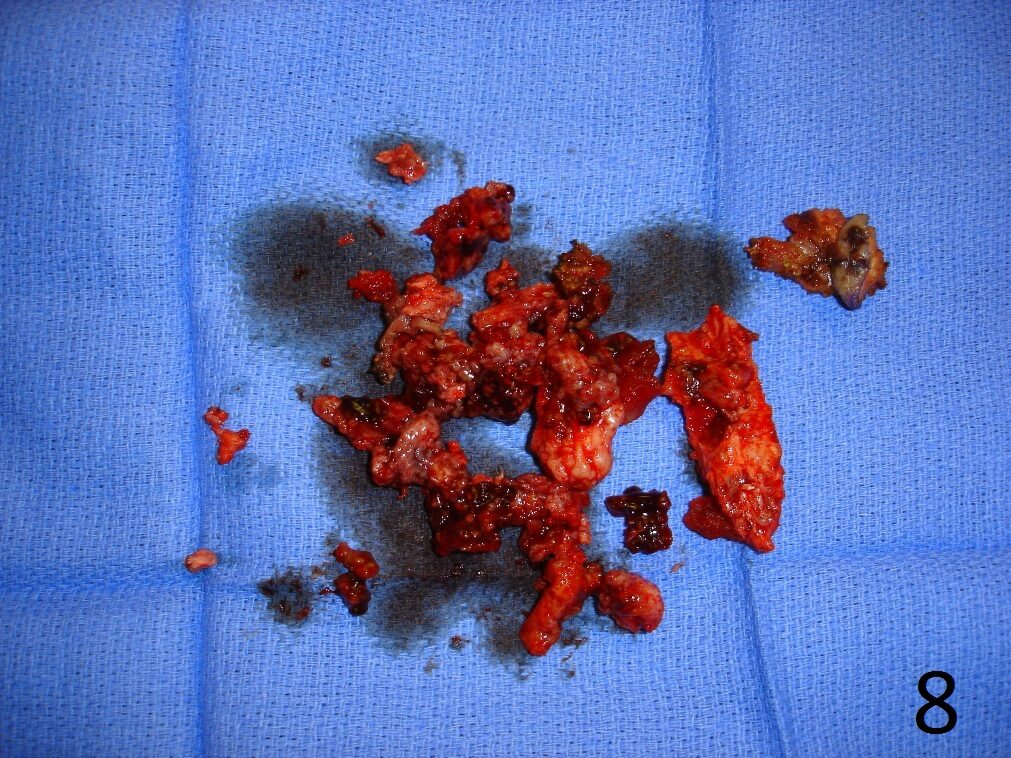

TREATMENT (Fig. 6-12)

• Wide resection recommended

• Possible/low recurrence

• Excision with curettage alone has recurrence rate of 40%

• Addition of cryosurgery to a curettage may lower the recurrence rate

• Role of radiation and chemotherapy are unclear

• Amputation for multiply recurrent tumors or those that are unresectable

Fig. 6-12: Intraoperative photograph of the lesion (Fig. 6) and steps of the treatment (Fig. 7-12), excision, cryosurgery, gross specimen and cemented internal fixation